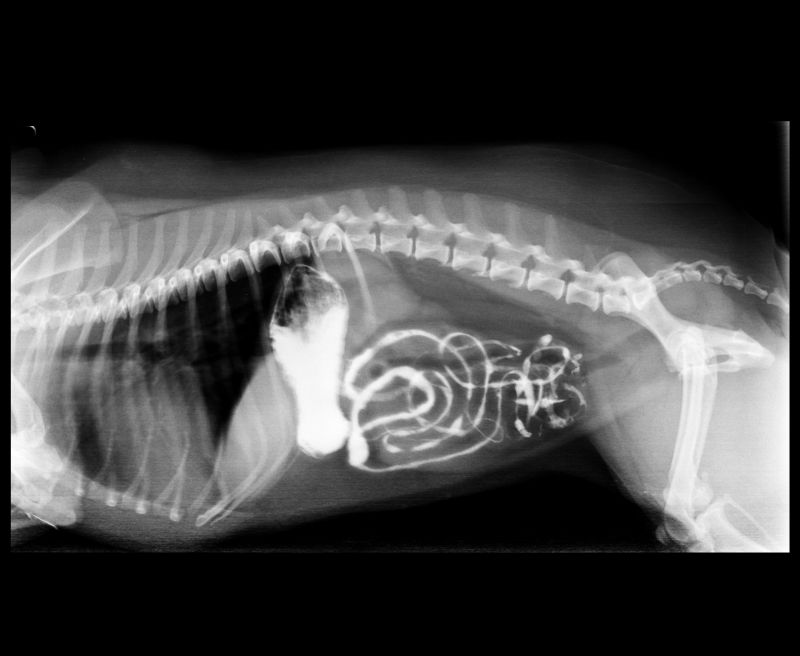

Abnormal Pathology on your pet

Shown on x-ray images which we have taken over the years.

Some interesting patient cases